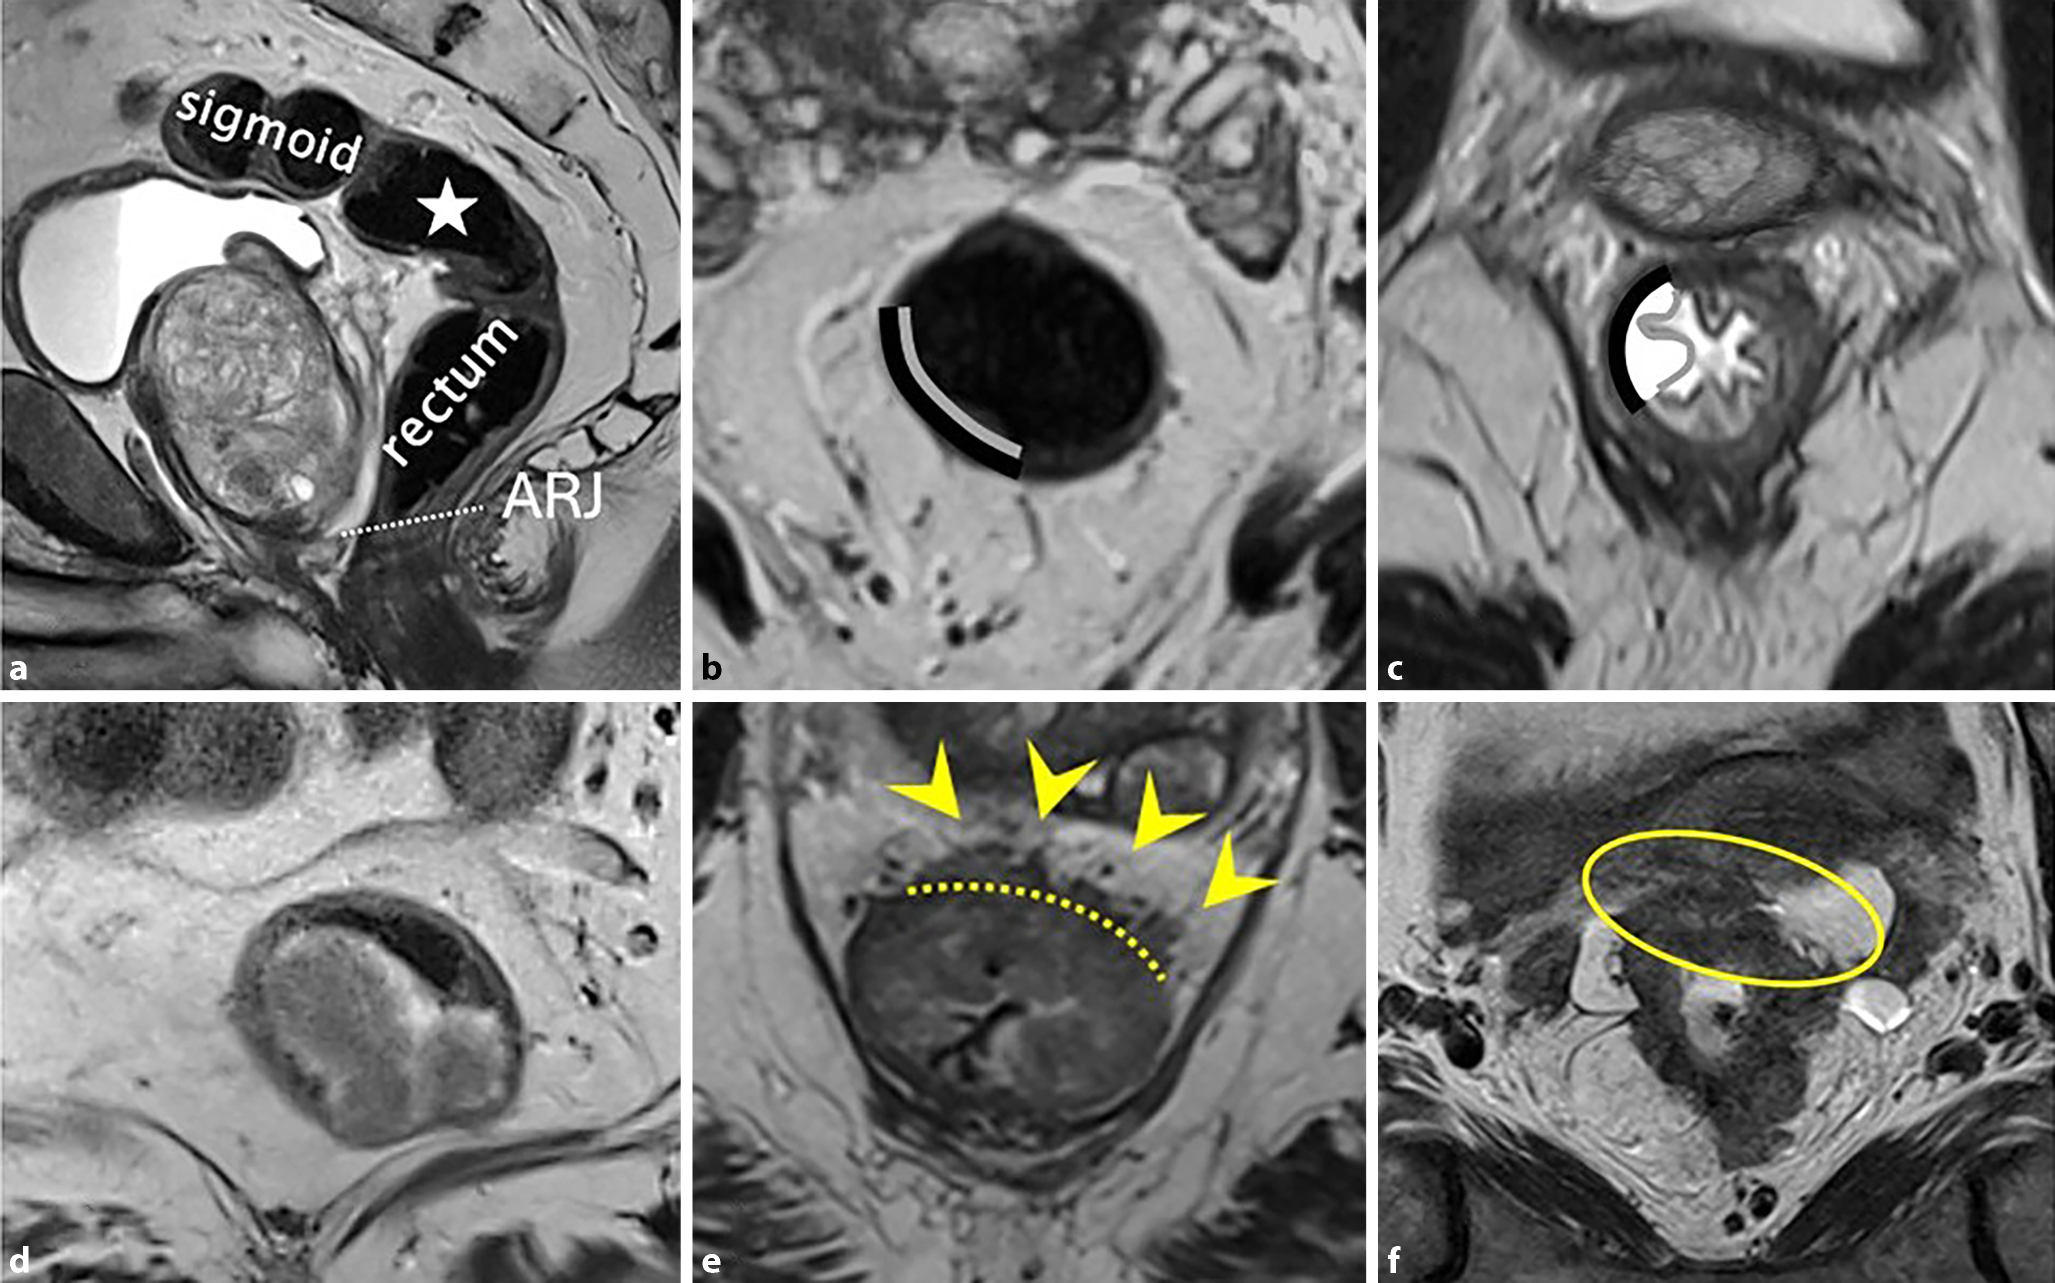

Abb. 3

a Sagittale T2-gewichtete Aufnahme eines gesunden männlichen Rektums, die den Sigmoid-Rektum-Übergang (Stern) zeigt. Die weiße, gestrichelte Linie markiert die anorektale Übergangszone (ARJ). b Normale, zweischichtige Morphologie des Rektums in der MRT. c Im Vergleich dazu eine Rektumwand mit ödematös veränderten, dreischichtigen Aussehen (von innen nach außen: Mukosa, Submukosa, Muscularis propria) auf axialen T2-gewichteten MRT-Aufnahmen. d Ein 63-jähriger Patient mit einem polypoiden Tumor, der als Tumorstadium T1–2 beurteilt wird. Die Submukosa ist nicht eindeutig sichtbar, wodurch eine genaue Differenzierung zwischen T1 und T2 unmöglich wird. e Axiale T2-gewichtete Bilder eines Low-risk-T3ab-Tumors, der sich von etwa 12 bis 2 Uhr (gelbe Pfeilspitzen) über die Muscularis propria (gestrichelte Linie) hinaus erstreckt, mit einer extramuralen Invasionstiefe von unter 5 mm. f Eine 78-jährige Patientin mit einem cT4b-Rektumkarzinom, basierend auf der Invasion des Uterus (gelber Kreis)

Die distale Begrenzung des Rektums hin zum Analkanal ist ebenfalls ein wichtiger Bestandteil der Befundung. Die makroskopisch sichtbare Grenze zwischen Rektum und Analkanal, die Linea dentata, ist radiologisch nicht abgrenzbar. Eine weitere, ca. 2 cm oral der Linea dentata gelegene Begrenzung stellt der anorektale Übergang dar (Abb. 3a). Hierzu kann in der sagittalen T2-gewichteten Sequenz eine imaginäre Linie zwischen dem Unterrand des Os coccygis und Os pubis eingezeichnet werden. Für die Therapieplanung sind zwei Punkte essenziell: einerseits das Vorhandensein einer Infiltration des Rektumkarzinoms in den Analkanal (und welchen Teil davon) und andererseits der Abstand zwischen Rektumkarzinom und Beginn des Analkanals. Der Abstand zum Analkanal bestimmt das operative Vorgehen und entscheidet, ob eine tiefe vordere Resektion und Anastomose durchgeführt werden kann.

Ausdehnung

Die drei wichtigsten Schichten der Rektumwand sind die innen befindliche Mukosa, Submukosa und die umgebende Muscularis propria [3]. Bei der routinemäßigen MRT des Rektums erscheint die Wand normalerweise als zweischichtige Struktur, wobei die Muscularis propria ein hypointenses Signal zeigt (Abb. 3b). Die Mukosa und Submukosa sind in der Regel nicht unterscheidbar, es sei denn, es liegt ein submukosales Ödem vor, das ihre Differenzierung als getrennte Schichten ermöglicht (Abb. 3c). Das Tumorstadium („T“ innerhalb der TNM-Stadieneinteilung) wird anhand der Tiefenausdehnung der Tumorinfiltration innerhalb dieser 3 Schichten definiert. Das Tumorstadium ist ein wichtiger Faktor in der Entscheidung der besten, individuellen Behandlungsoption und zur Risikoabschätzung. Tumoren, die auf die Submukosa (T1) beschränkt sind oder sich maximal in die Muscularis propria ausdehnen, aber nicht darüber hinaus (T2), werden als Tumoren im Frühstadium bezeichnet. Diese können entweder endoskopisch abgetragen oder mittels totaler mesorektaler Exzision chirurgisch entfernt werden. Die begrenzte Sichtbarkeit der einzelnen Schichten der Darmwand ist ein entscheidender Faktor, warum in der MRT in der Regel nicht zwischen T1- und T2-Tumoren unterschieden werden kann, weshalb diese häufig gemeinsam als Stadium T1–2 befundet werden (Abb. 3d). Eine genaue Unterscheidung zwischen T1 und T2 ist durch eine ergänzende endorektale Ultraschalluntersuchung möglich. Wenn der Tumor die Muscularis propria durchbricht und das mesorektale Fettgewebe infiltriert, handelt es sich um einen T3-Tumor. Diese Tumoren können von Tumoren mit geringem Risiko und begrenzter extramuraler Invasion (T3a und T3b; Abb. 3e) bis hin zu Tumoren mit höherem Risiko und ausgedehnterer extramuraler Invasion (T3c und T3d) reichen. T3-Tumoren können auch die mesorektale Faszie (MRF) infiltrieren. T4-Tumoren zeigen eine Infiltration in angrenzende Strukturen oder Organe (Abb. 3f). Die Ausdehnung des Tumors entlang der Rektumwand wird wie auf einem Ziffernblatt einer Uhr bezeichnet (z. B. von 4–6 Uhr).